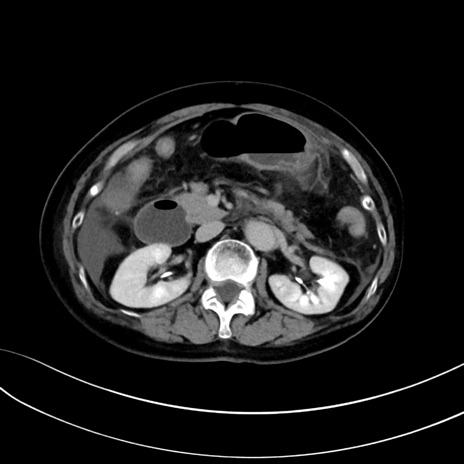

症例13 CT(横断像)1日半後